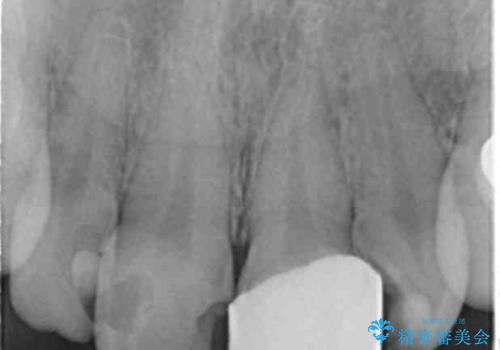

- 欠けてしまった前歯のラミネートベニヤと見た目の改善を求めて来院されました。

歯の大きさの不揃いと、虫歯の再発を認めたためラミネートのやりかえではなく一挙に問題の解決のできるジルコニアクラウンでの治療を計画します。